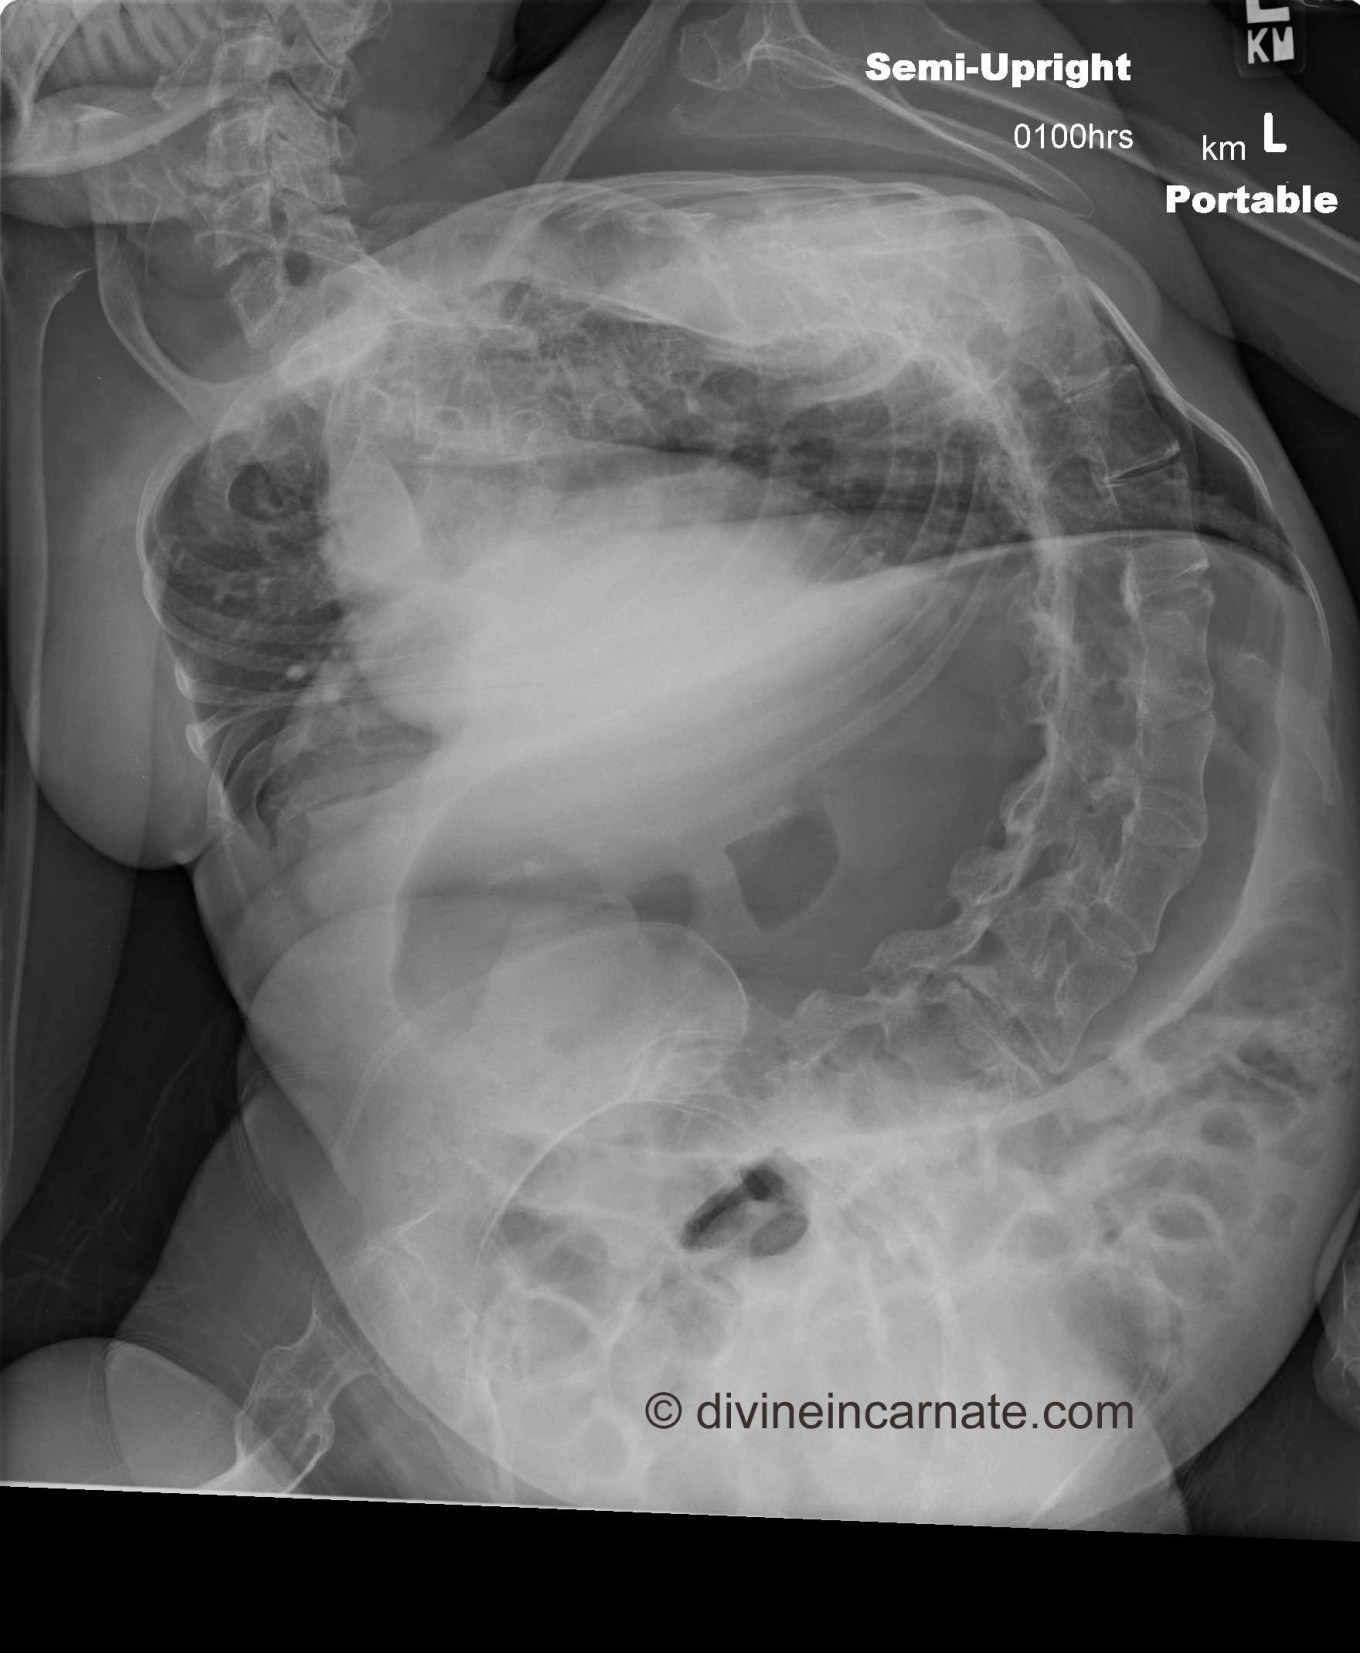

Recently writing about my current medical issues and concerns, I’ve decided that perhaps it is true: a picture is worth a thousand words. So, I’m sharing with all of you a picture of my body – an x-ray image of my torso. Although the image was taken in order to look for pneumonia, you can see my spine in it and, so, the interesting twists and turns of my backbone and deformity of my ribs. (Don’t say that I ever held back in bearing myself to you, letting you know me inside and out!)

Is it any wonder that surgery is not an option for me?